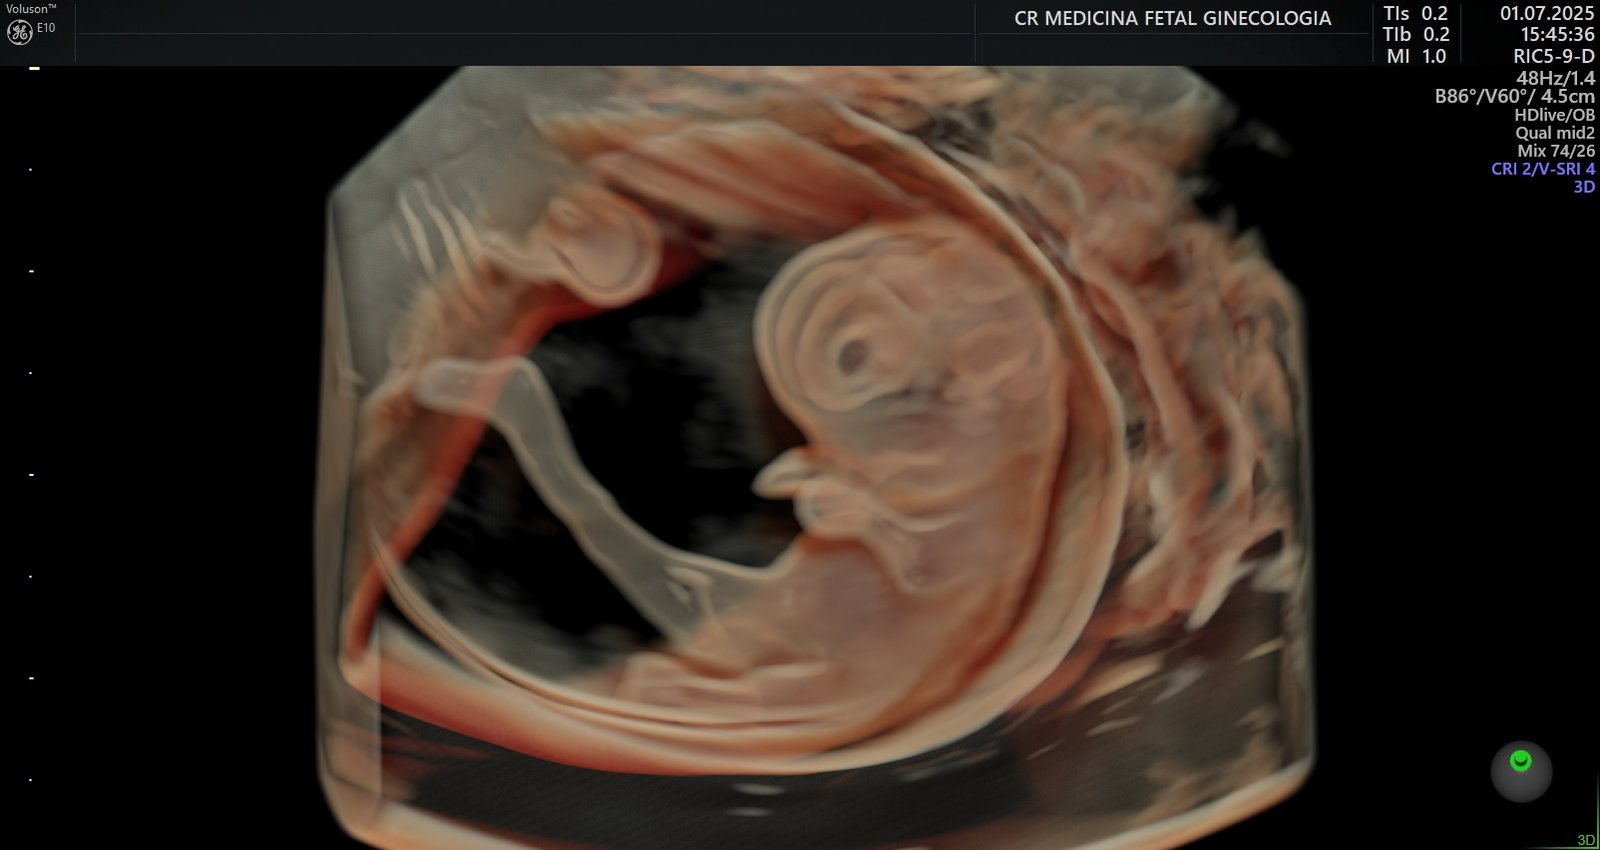

Ultrassonografia 3D e 4D: Permite visualizar o bebê em alta definição, em tempo real, em qualquer idade gestacional, proporcionando um vínculo ainda maior entre a família e o bebê.

Avaliações embrionárias e fetais completas: Análises aprofundadas desde os estágios iniciais da gestação, garantindo que cada fase seja acompanhada com precisão.